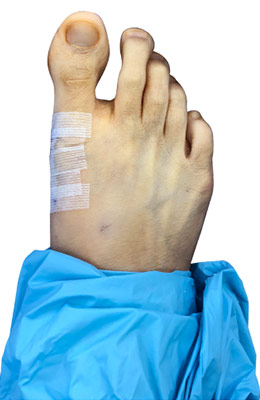

Before

Minimally Invasive Bunion Surgery before

After

Minimally Invasive Bunion Surgery after

Minimally Invasive Bunion Surgery featuring the miniBunon™ System and Tailors Bunionectomy

Melissa is a 32-year-old businesswoman who could not be off her foot post-surgery, yet she had a severely painful bunion. We performed our miniBunon™ System (our trademarked minimally invasive bunion surgery) and had a dramatic correction with no downtime. Melissa continued to work after her bunion surgery and was back in shoes and full activity at 5 weeks. Melissa could not believe the results of her Bunionectomy resulting in no bony bump, no scar and amazing motion. “After” picture taken immediately following surgery. Note the bunion and bunionette (Tailor’s bunion) in the before picture.